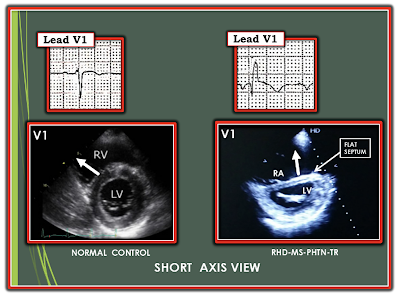

- The 3rd important finding in ECG #2 is the small-but-real initial negative deflection (q wave) for the QRS complex in lead V1, which makes for a "qR" pattern. The presence of a qR pattern in lead V1 in a patient with RVH is a marker of severe pulmonary hypertension, with increased risk of mortality (Waligóra et al: J Electrocardiol — 50(4): 476-483, 2017).

- The 4th important finding in ECG #2 is AFib (irregularly irregular rhythm without P waves) — because this completes a clinical Triad (AFib + RVH + qR in V1) that strongly suggests RHD (Rheumatic Heart Disease) with severe MS (Mitral Stenosis) and resultant pulmonary hypertension until you prove otherwise! This is because as mitral stenosis progresses (and mitral valve area decreases) — left atrial size (and resultant LA pressure) progressively increase — with proportional increase in pulmonary arterial and venous pressures. Clinical decompensation may rapidly occur once AFib develops, as this eliminates the "atrial kick" which had provided important enhancement of left ventricular filling that the patient depended on (CLICK HERE for an excellent review in the Cardiology Advisor by O'Gara & Udell on the diagnosis and clinical features of Mitral Stenosis).

- There is a physiologic reason why pulmonary hypertension from advanced mitral stenosis commonly results in a qR pattern in lead V1 (Figure-2).

- Both patients had RHD, with resultant severe mitral stenosis + pulmonary hypertension + RV dilatation with severe tricuspid regurgitation.

- This pathophysiology is easily predictable by the fact that: i) Both patients come from a country with a high prevalence of RHD (ie, they are both from India); and, ii) The ECG of each patient shows marked RVH with a qR pattern in lead V1 — as well as other ECG findings consistent with severe mitral stenosis (ie, AFib, RAA, LAA).